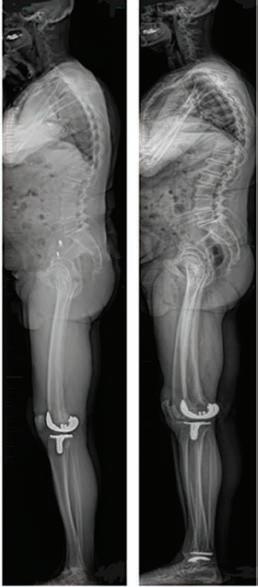

EOSedge is a precise, low dose imaging system that delivers full body images covering the full set of musculoskeletal and orthopaedic exams.

• Imaging complete in 20 seconds

• Full body images in standing position

• 24 hour report turnaround

• True 1:1 scale

Refer your patients now for lower dose imaging and better visualisation for diagnostic or surgical planning and post operative assessment.

• Low dose radiation

• Walk ins welcome

• All request forms accepted

• All scans are bulk billed